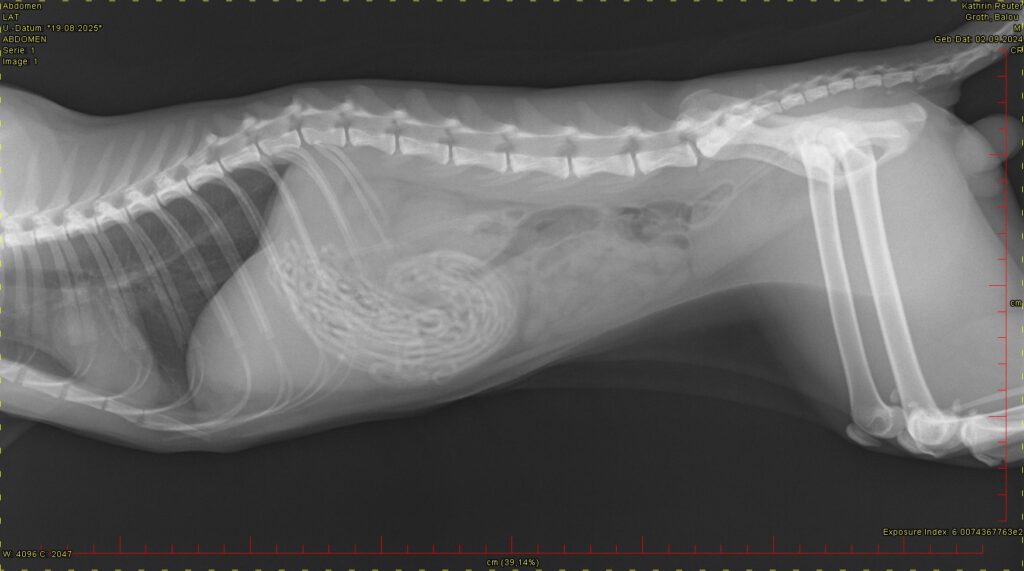

Nach der klinischen Untersuchung konnte der Palpationsverdacht auf Fremdkörper im vorderen Bauchraum im Röntgen bestätigt werden. Hier können wir strahlendichte Strukturen im Magen sehen.